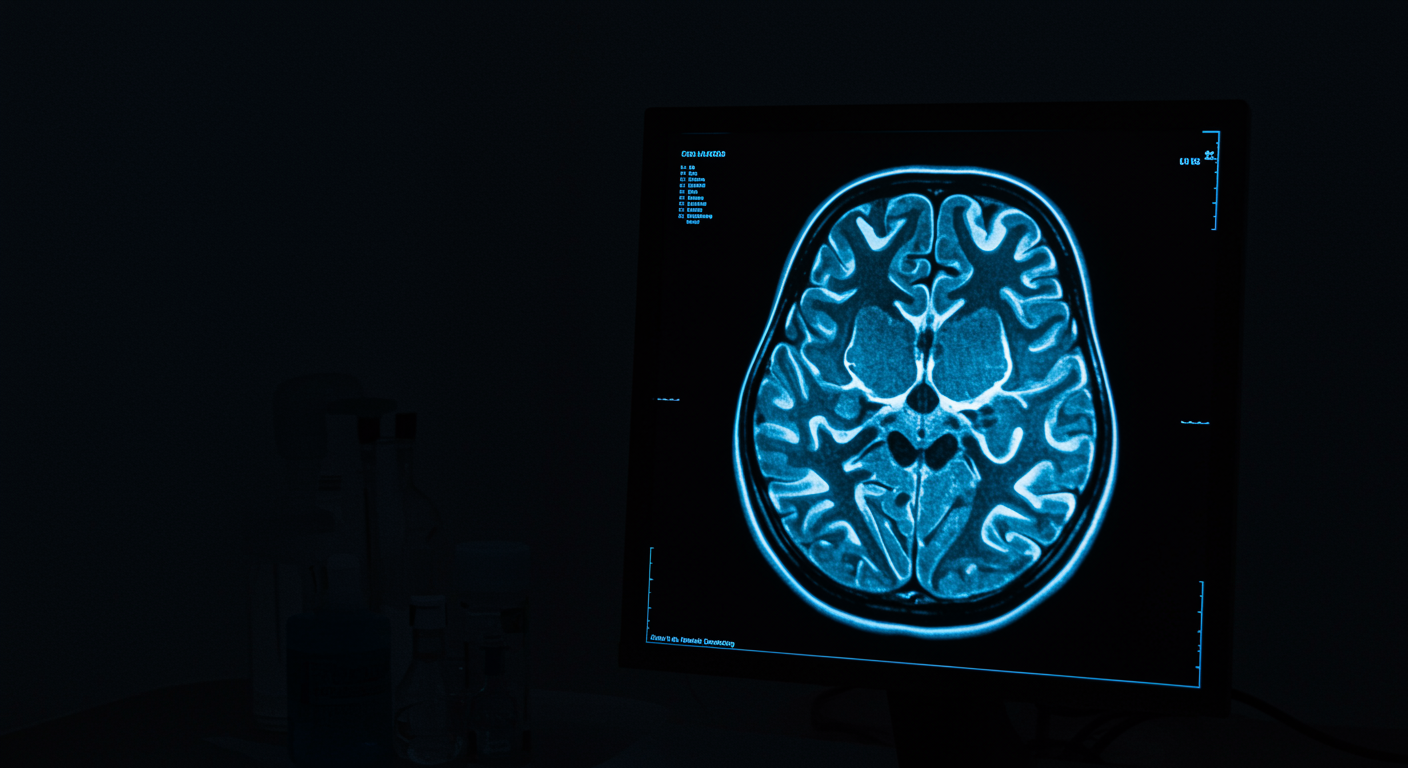

HPA Axis and Depression Across Women's Reproductive Life

Why Perimenopause Triggers Depression and How to Treat It